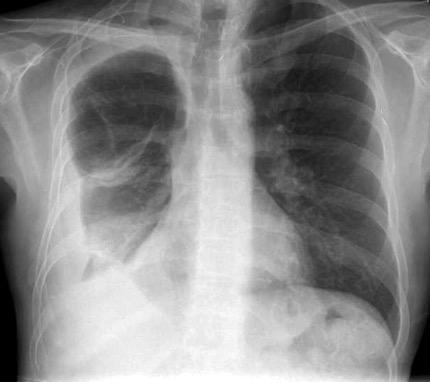

Derrame pleural 43-48% de pacientes con embolismo.

< 1/3 de hemitórax: 90%.(puede haber en lado opuesto).

Siempre exudados.

75% de los pacientes con TEP y derrame pleural tienen dolor pleurítico.

La disnea desproporcionada

Joroba de Hampton

Hallazgo muchas veces incidental.